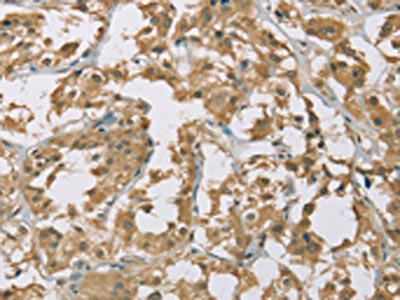

The image on the left is immunohistochemistry of paraffin-embedded Human liver cancer tissue using CSB-PA915667(EIF5 Antibody) at dilution 1/25, on the right is treated with fusion protein. (Original magnification: ×200)

The image on the left is immunohistochemistry of paraffin-embedded Human thyroid cancer tissue using CSB-PA915667(EIF5 Antibody) at dilution 1/25, on the right is treated with fusion protein. (Original magnification: ×200)